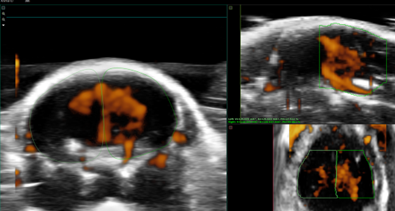

Custom services Cardiology

Myocardial Blood Saturation, Ischemia, Heart occlusion & Strain Analysis

Using the Vevo F2 Lazr-X system, we provide advanced assessment of myocardial oxygenation, ischemia, and cardiac mechanics in rodent models. Through photoacoustic imaging (PA mode) combined with EKV (Electrocardiogram-Gated Kilohertz Visualization), we measure oxygen saturation and hemoglobin concentration within cardiac tissue, enabling precise detection of ischemic regions. Additionally, we offer Vevo Strain analysis, a high-resolution speckle-tracking technique for quantifying myocardial deformation and contractility, providing deeper insights into cardiac function under physiological or stress conditions.

This integrated approach supports studies on cardiovascular disease progression and therapeutic interventions.

Fetal Echocardiography

For developmental studies, it is possible to monitor living mouse/rat embryos in uterus and follow the development of cardiac structures as well as changes in blood flow velocities in the heart and umbilical artery. An application of high-frequency probes with conventional 2D and pulse-wave Doppler imaging of the fetus can provide excellent information on the early development of cardiac structures.